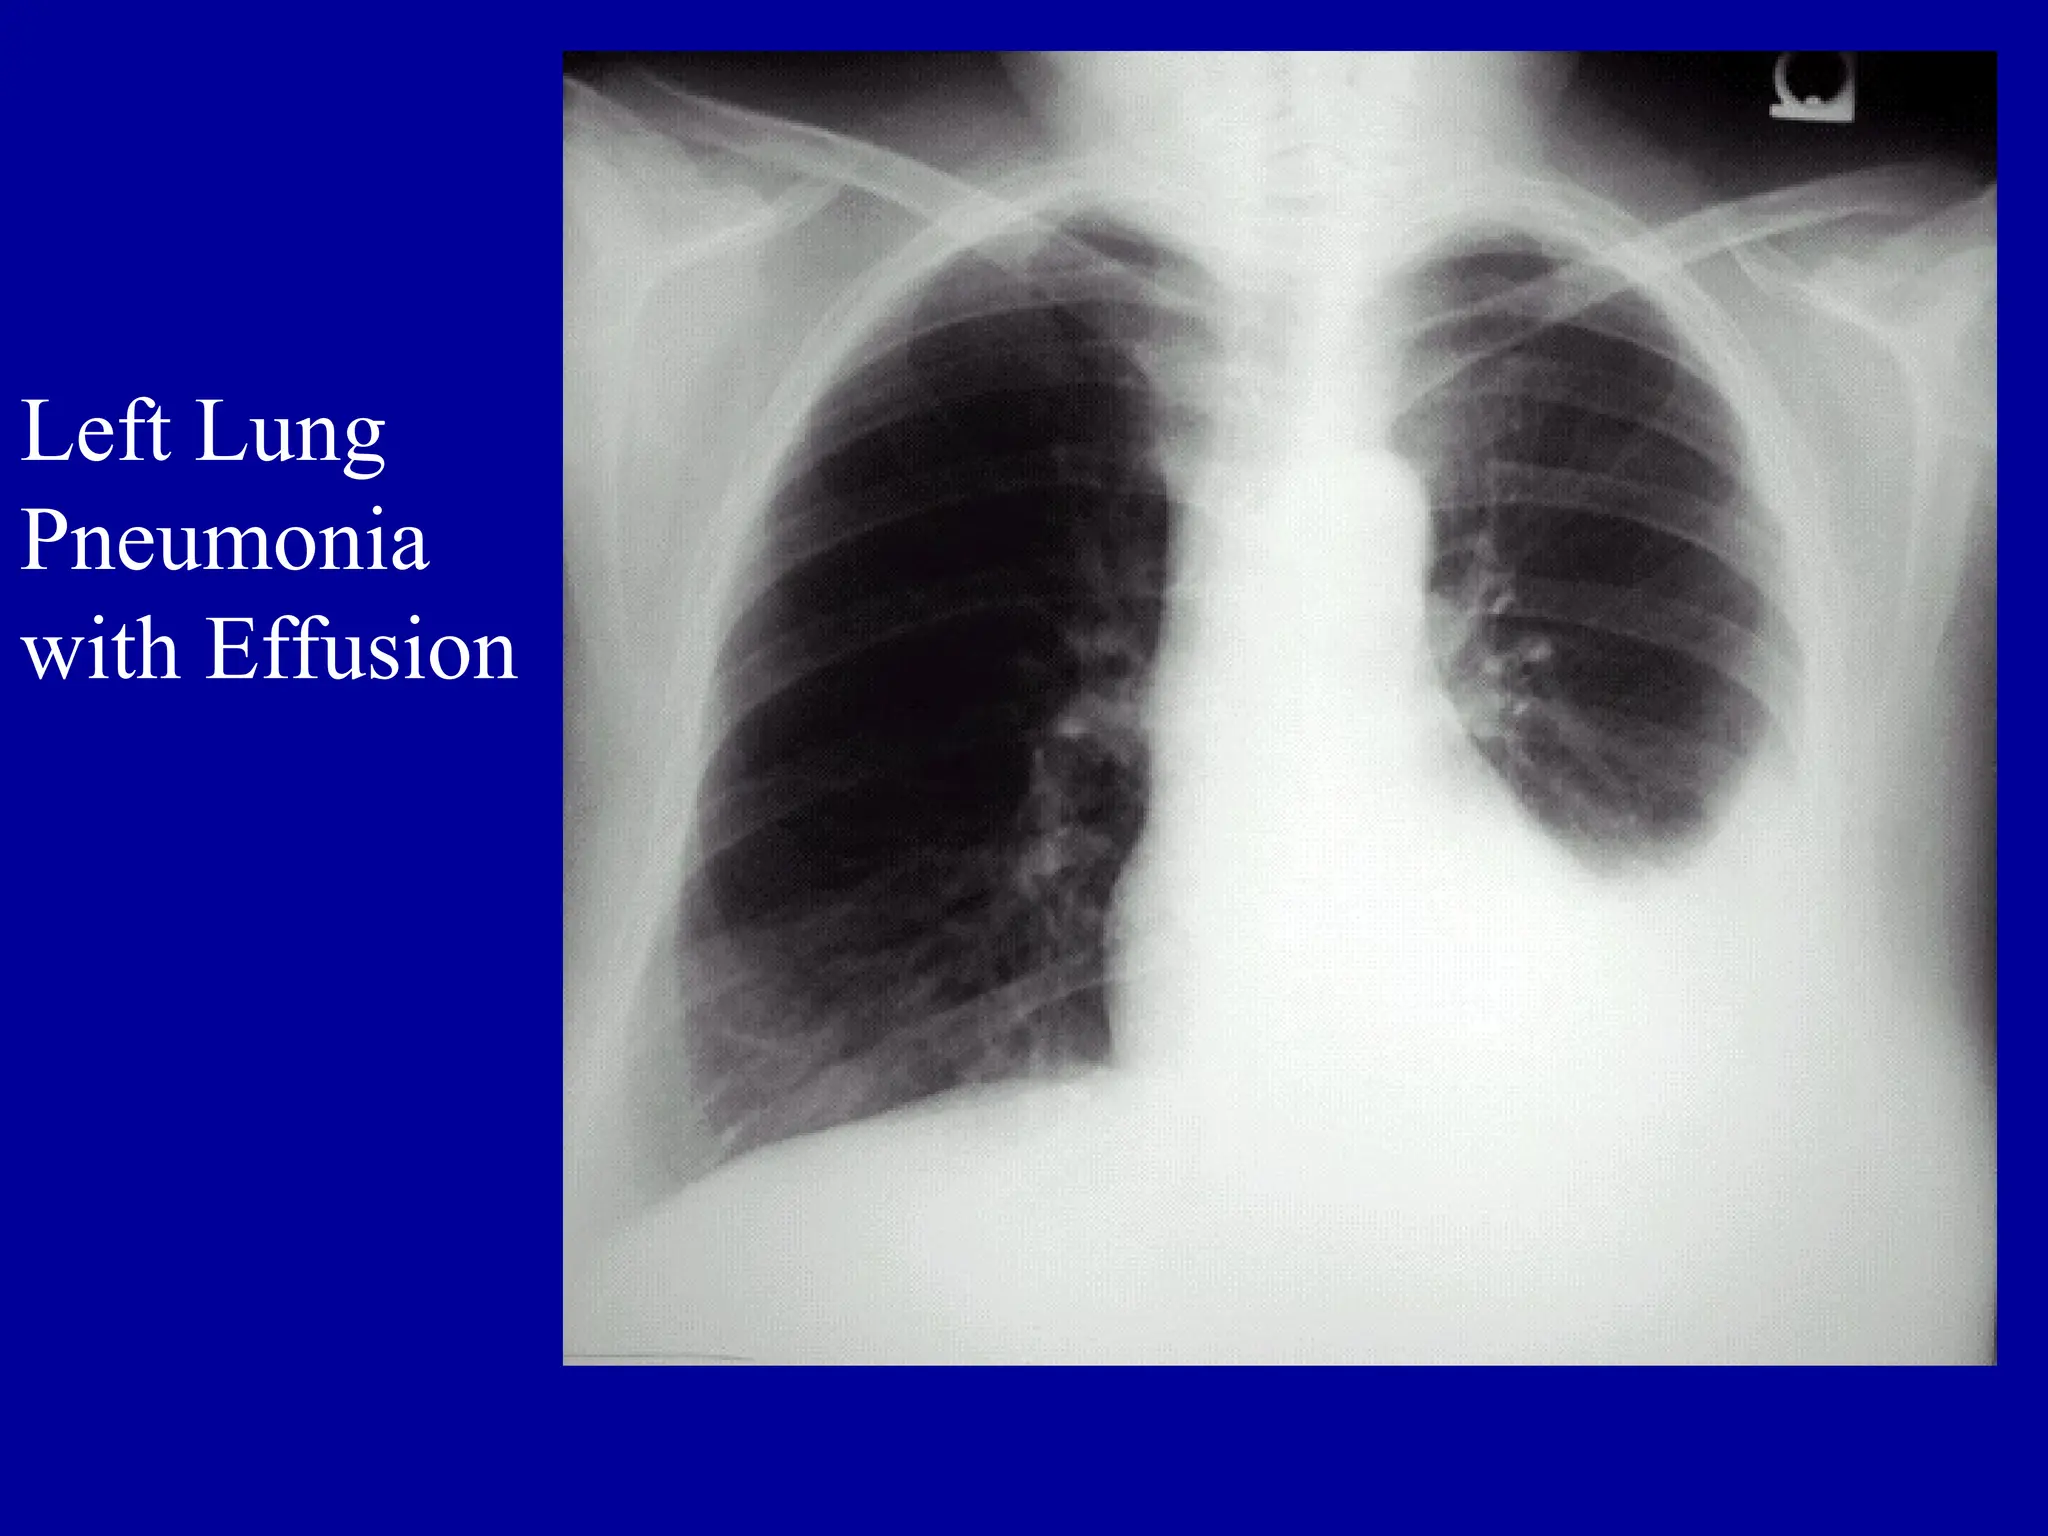

Left Lung

Pneumonia

with Effusion